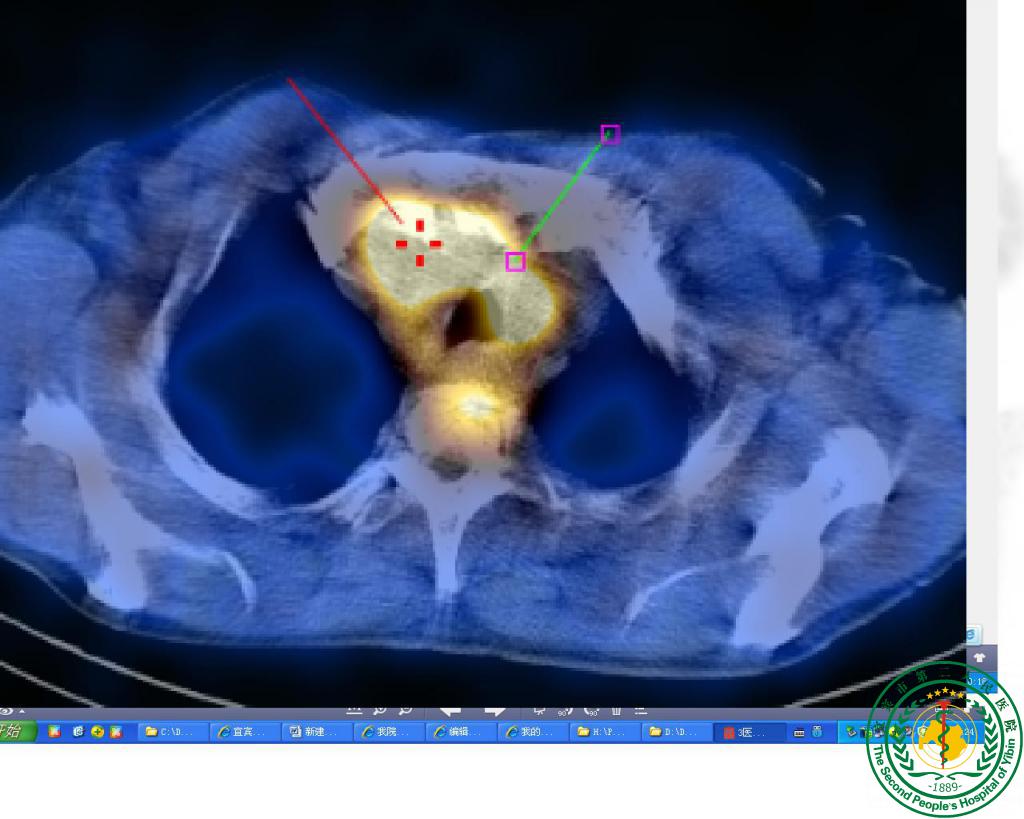

“鹰眼”派特CT确诊疑难“肺结节”一例

宜宾市第二人民医院 图文